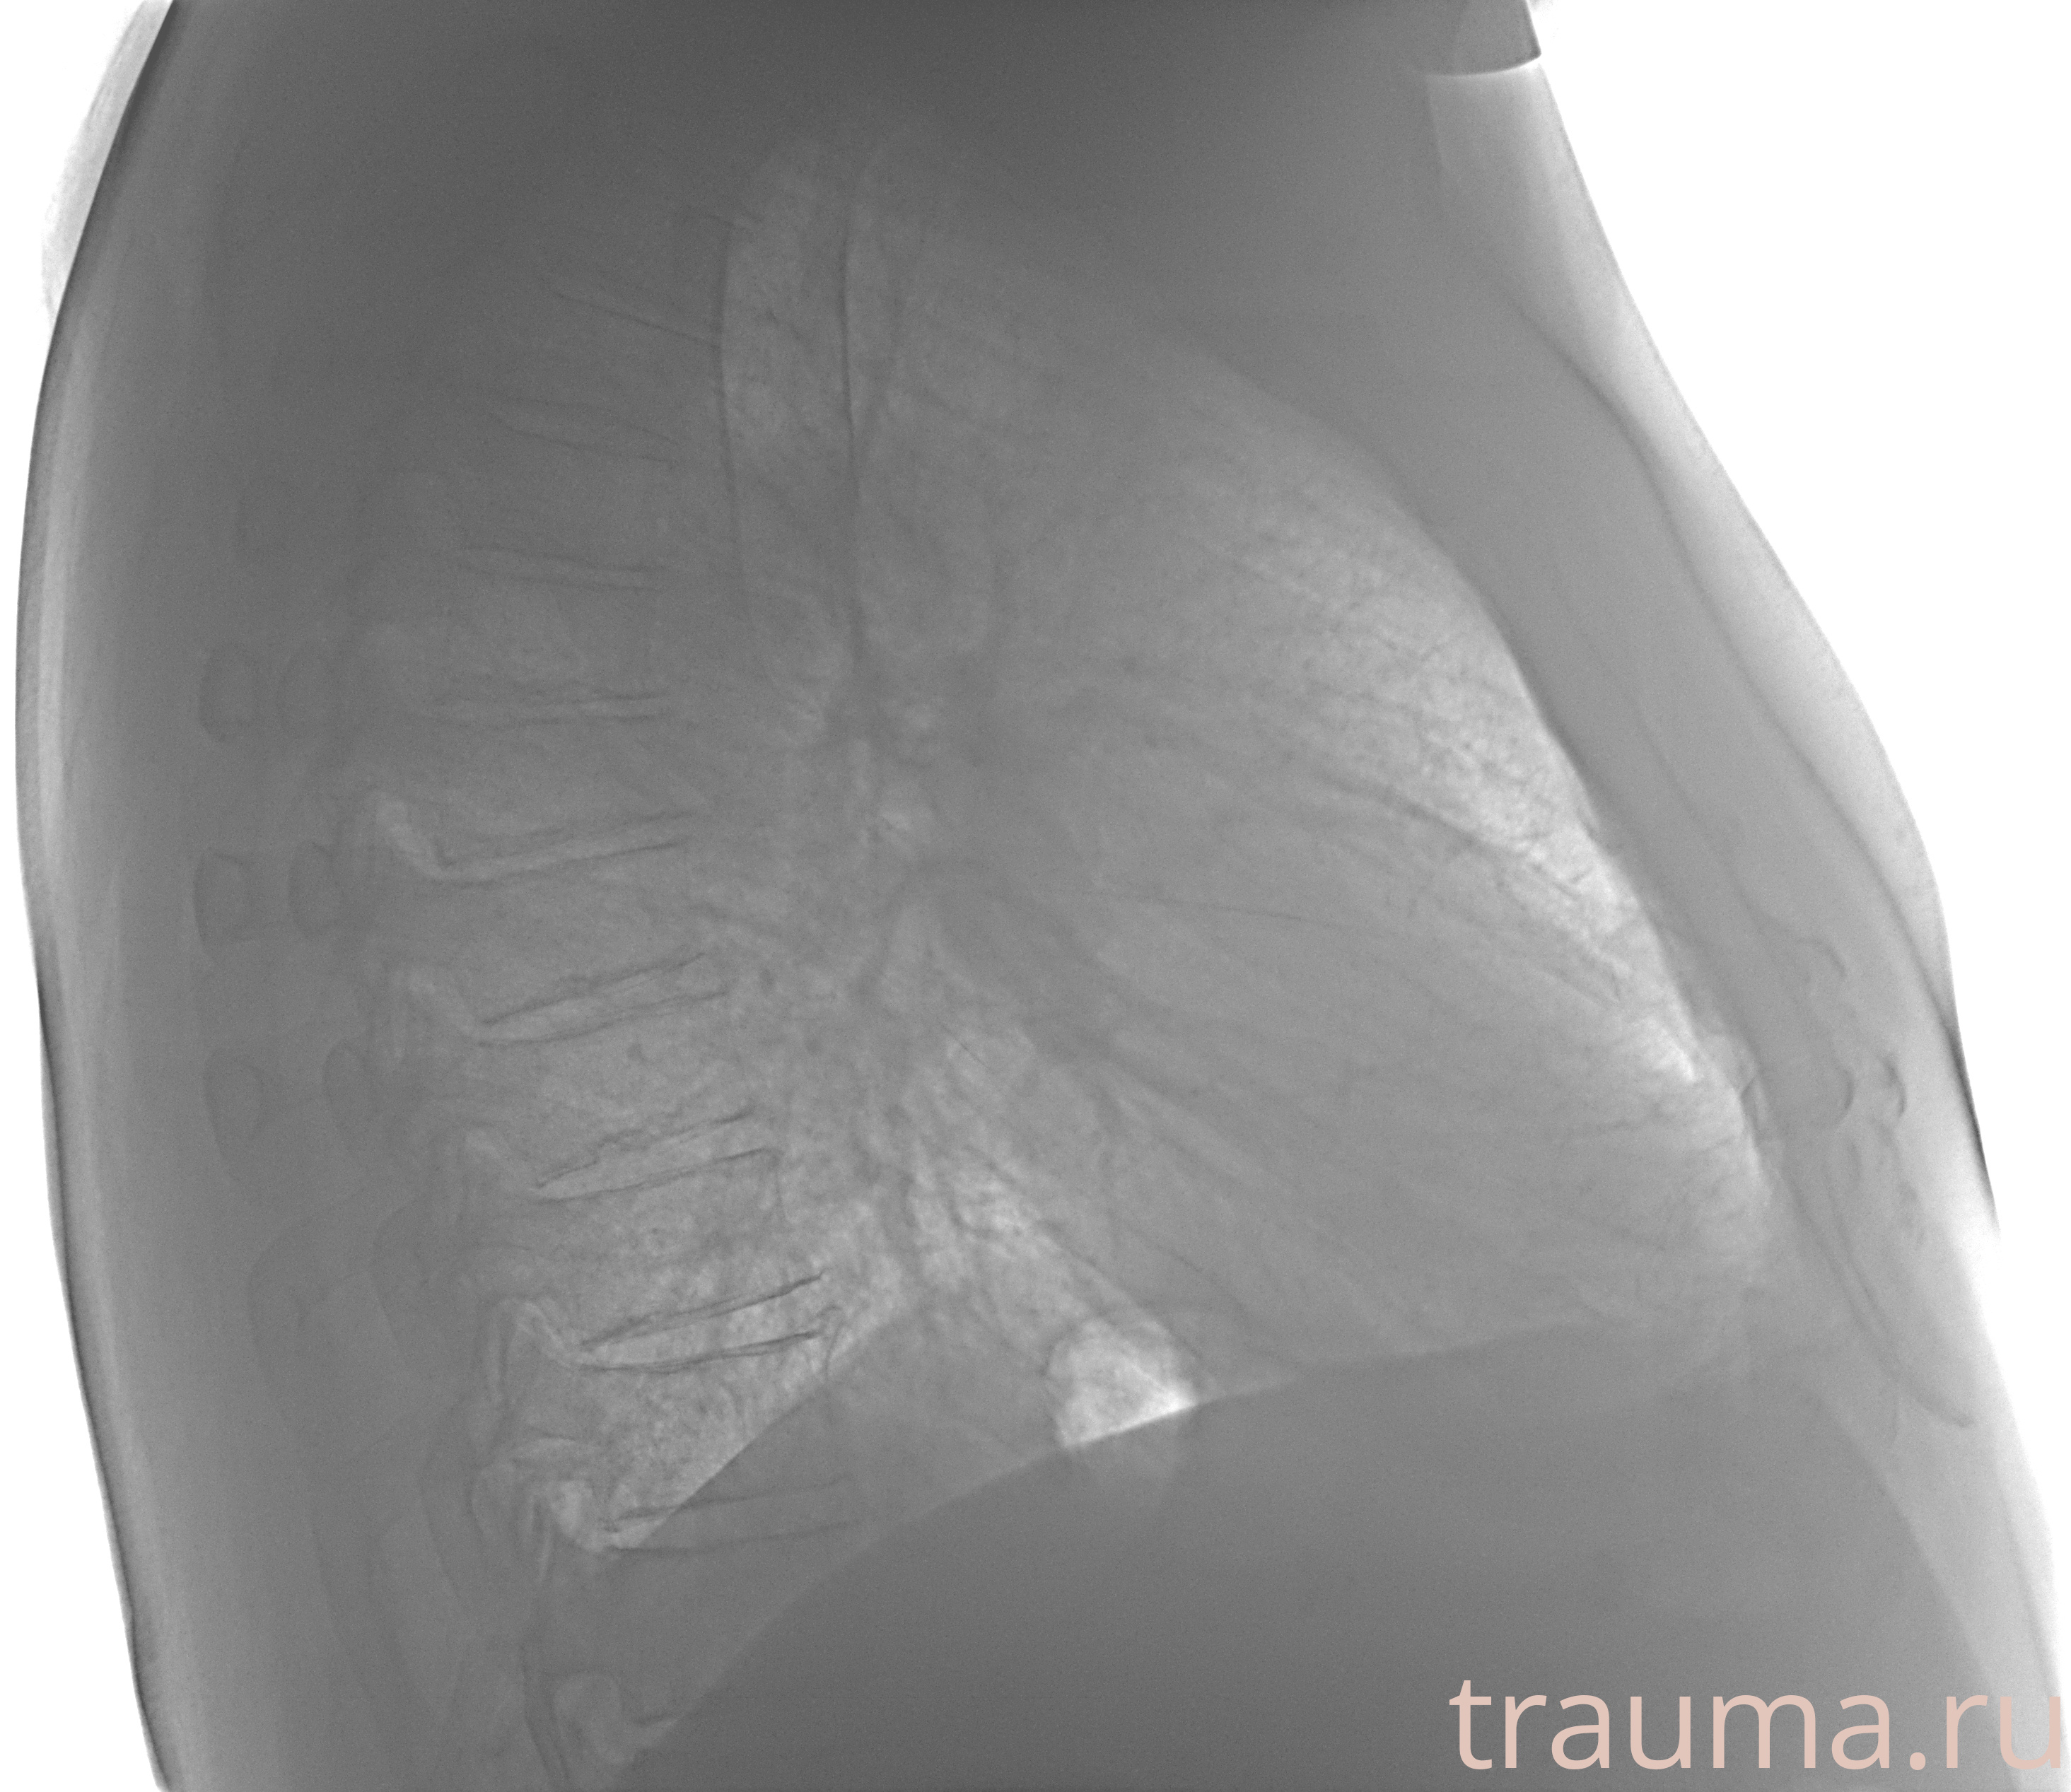

Рентгенограммы

Рентген на дому: по вашему адресу приезжает врач-рентгенолог, травматолог-ортопед с мобильным рентгеновским аппаратом, проводит диагностику травмы или заболевания, делает необходимые рентгенограммы, дает рекомендации по дальнейшему лечению. Получить качественные снимки в домашних условиях возможно благодаря уникальной методике, разработанной МосРентген Центром для института  Склифосовского

при переломе шейки бедра и пневмонии от компании МосРентген Центр - партнера Института имени Склифосовского